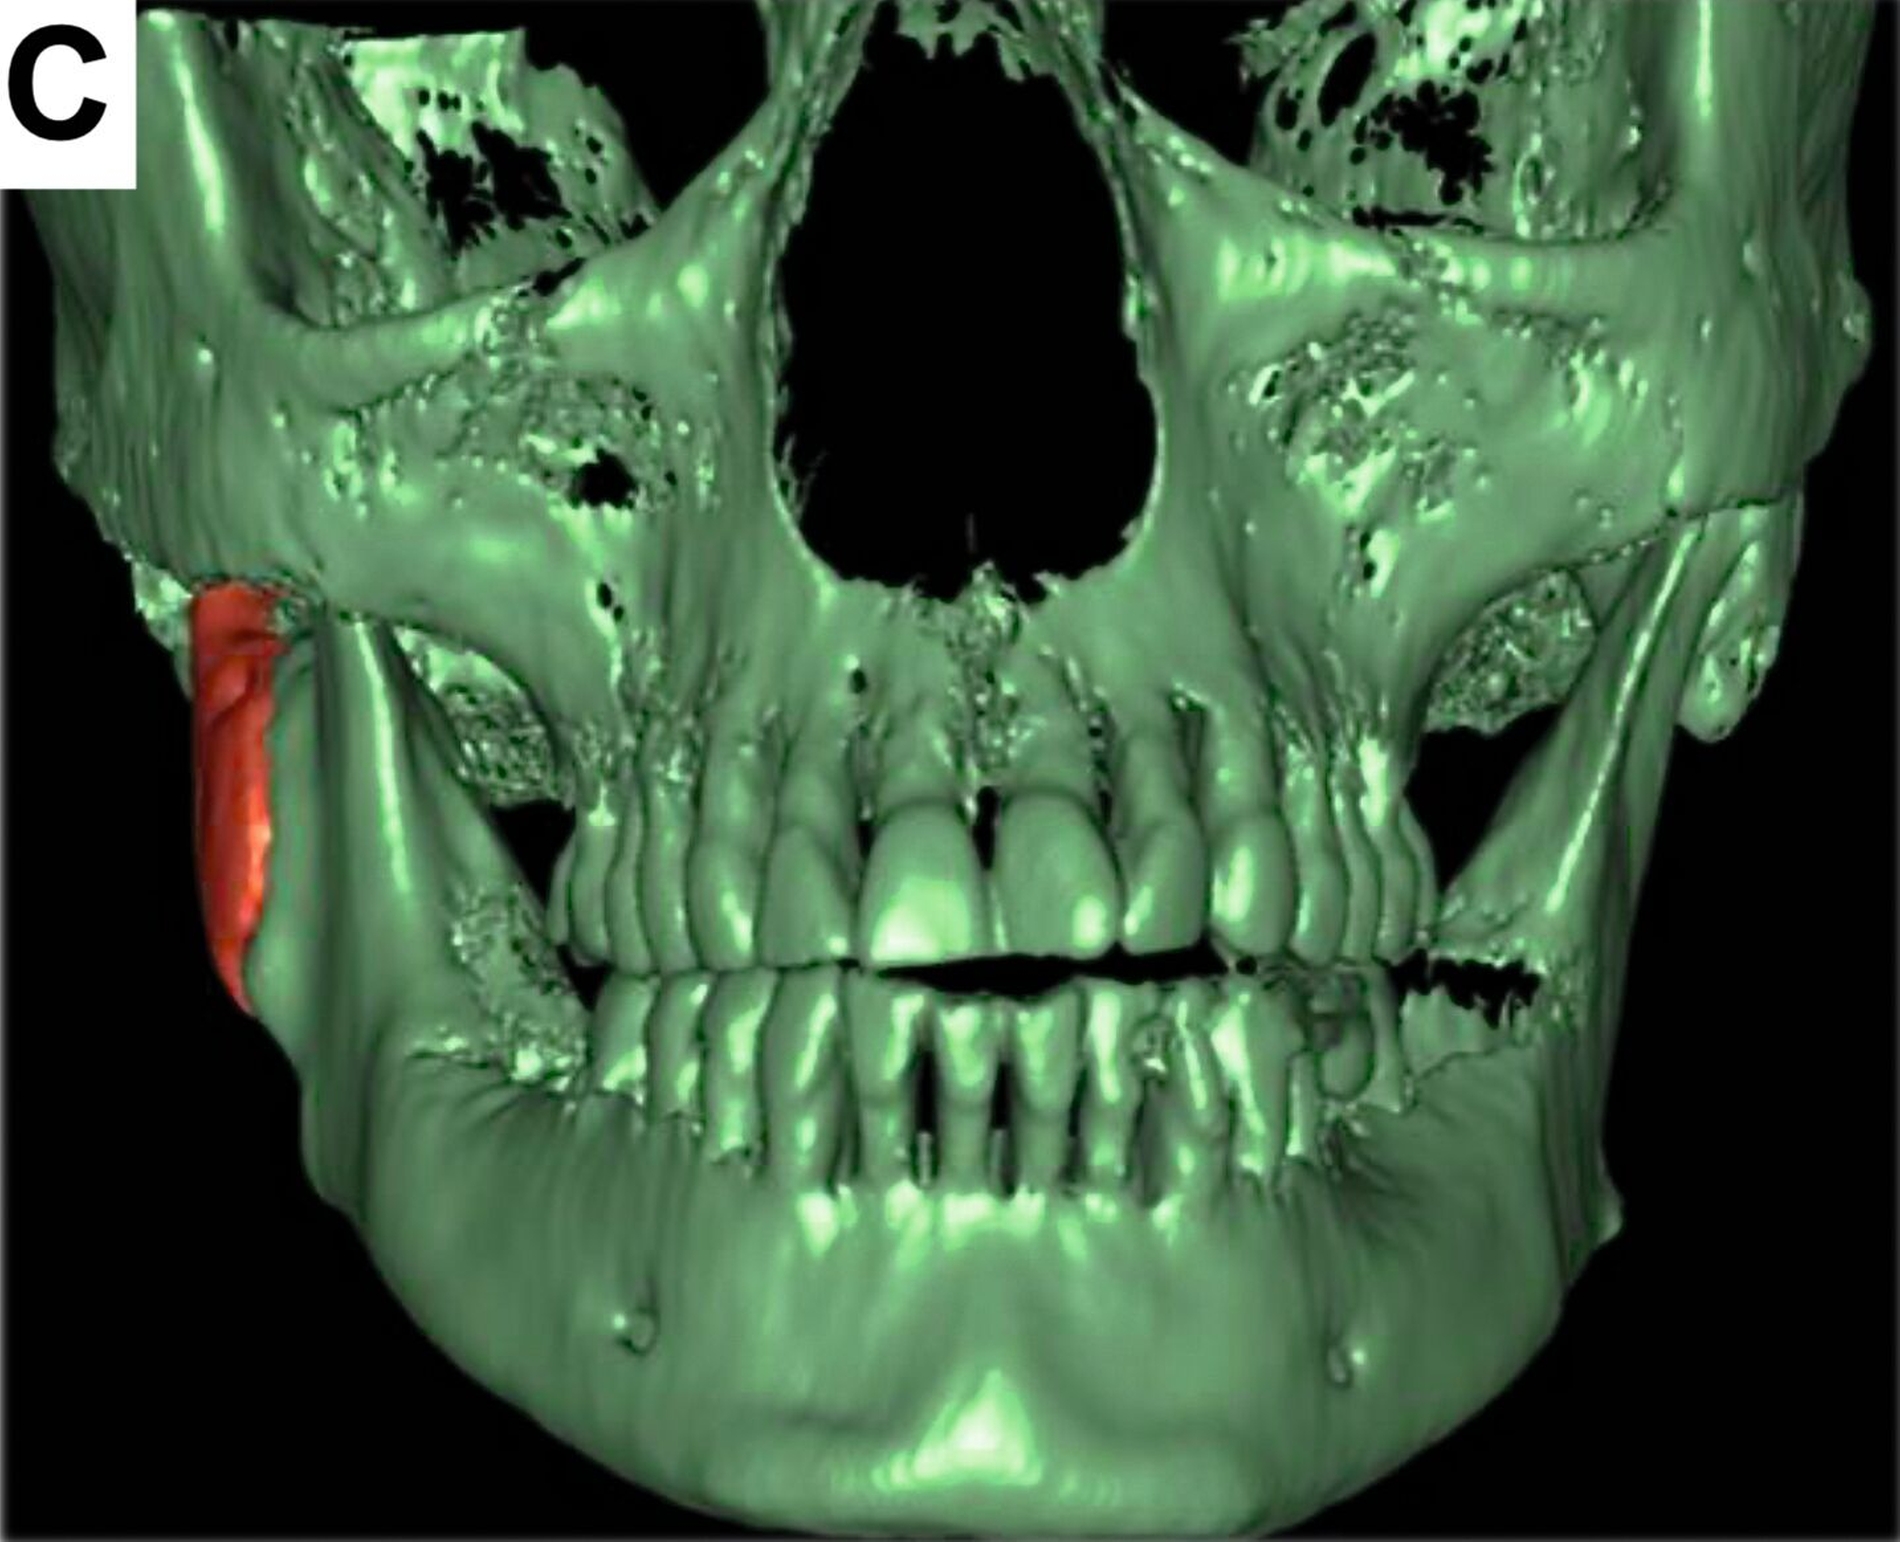

Nach einer achtmonatigen Konsolidierungsphase unter Verwendung einer Okklusionsschiene wurde zur Planung einer industriell gefertigten CAD/CAM-Kiefergelenk-Totalendoprothese ein Dünnschicht-CT durchgeführt (Abbildung 3).